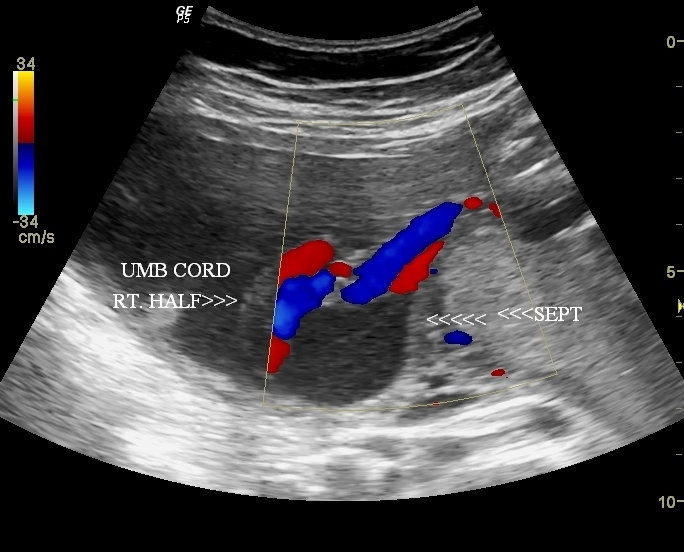

subseptate uterus with pregnancy

This is a third trimester pregnancy - 32 weeks with a partial septum in the fundus of the uterus dividing the uterus into a small right compartment and a large left one. The fetus occupies the left half of the uterus with part of the legs and umbilical cord in the right compartment.  These ultrasound images suggest pregnancy with subseptate uterus as the septum is incomplete and does not reach up to the internal os.

a septate or subseptate uterus is associated with increased incidence of premature delivery and also abortions. However most cases of septate uterus or subseptate uterus may have no difficulty conceiving.